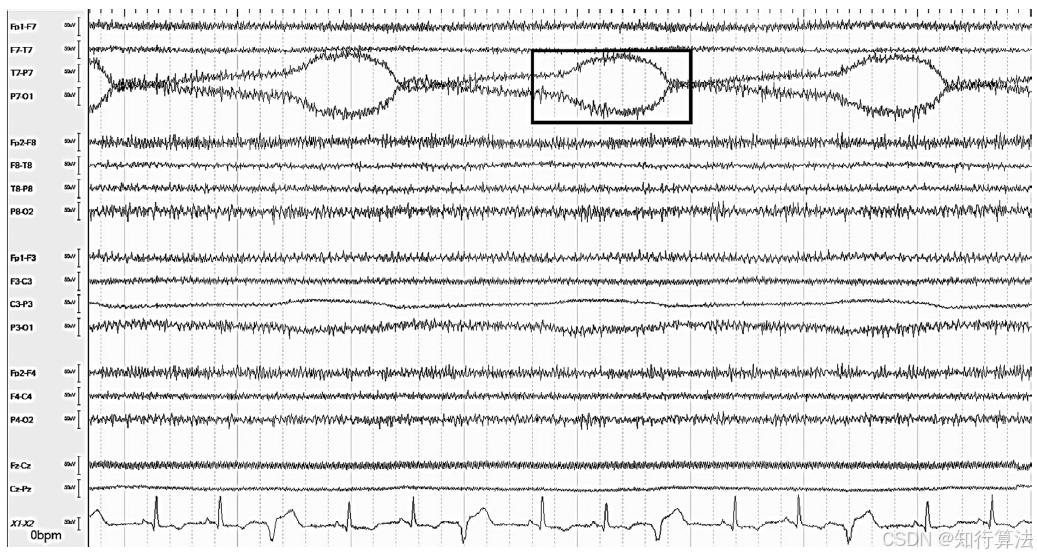

波形特征:典型的慢正弦δ波,可出现在单个或多个导联(图3)。

图3:多通道中的汗液伪迹